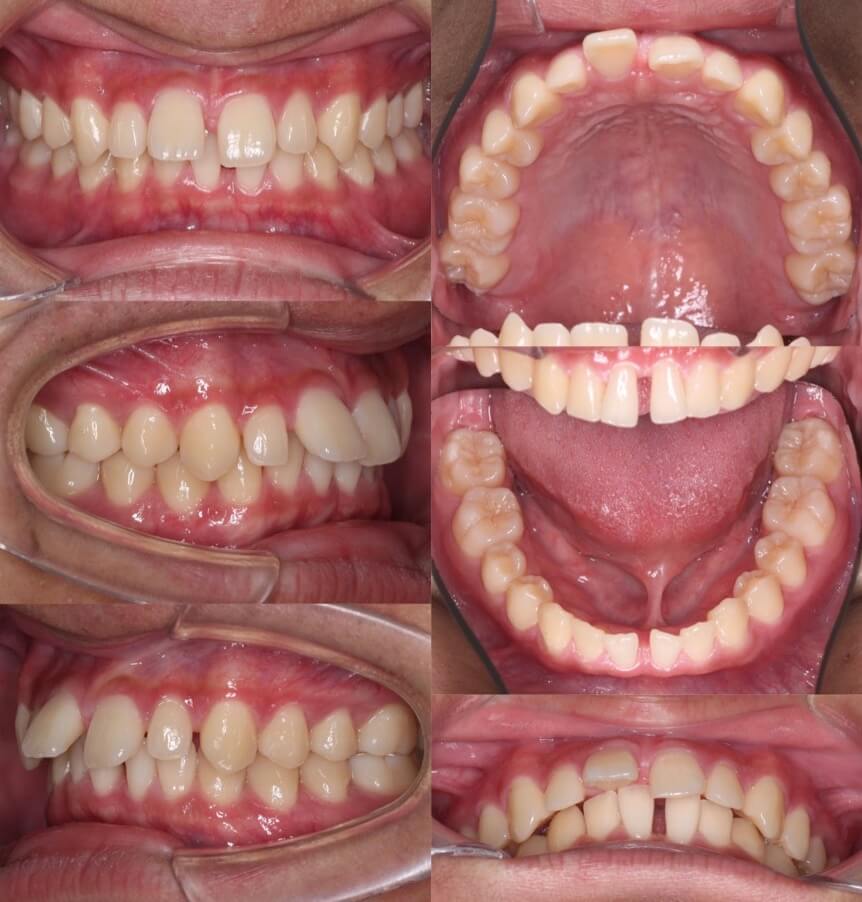

高校生男子・マウスピース型矯正装置

<症例概要>

主訴:すきっ歯・正中線のずれ

年齢・性別:大学生男性

治療方針:空隙閉鎖+右下歯列後方移動

治療装置:マウスピース型矯正装置(アライナー装置)

固定装置:III級顎間ゴム

治療期間:1年10か月

アライナー枚数:48+27+27ステージ (5〜7日交換)

リテーナー:上フィックスタイプ+上下クリアタイプ

治療費用:990,000(税込)

右下を後方移動させる事で、左にずれている下の歯並びの正中線を右側に移動させる計画です。

隙間が上の奥歯まであり奥歯のかみ合わせの問題もある少し難しいケースです。下の歯列を右側に回し込み上下の正中線を合わせながら隙間を閉じていきました。